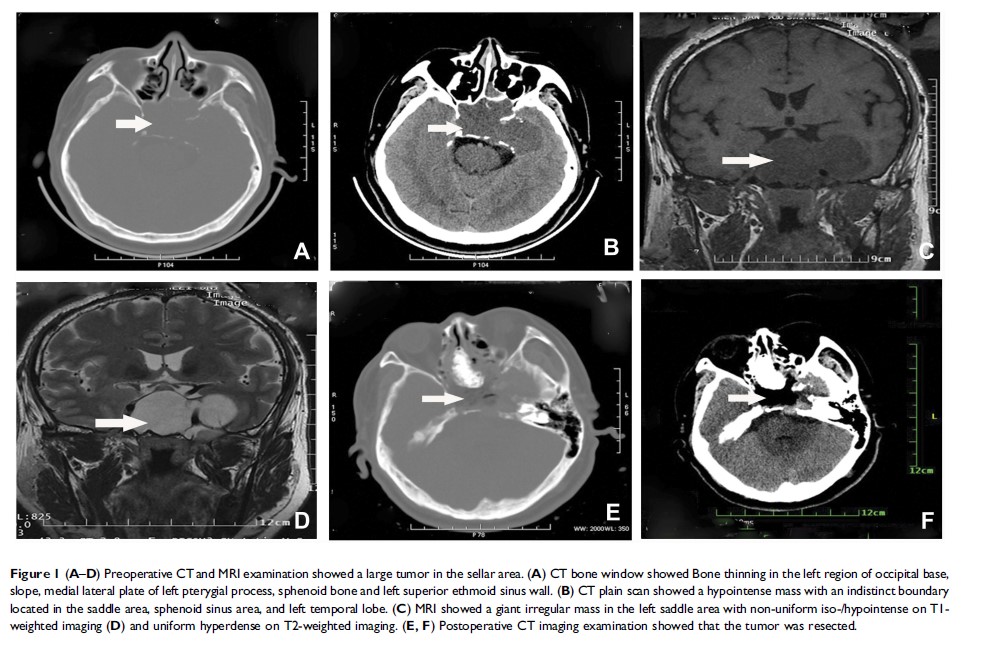

鞍区低度恶性软骨肉瘤:病例报告和文献回顾